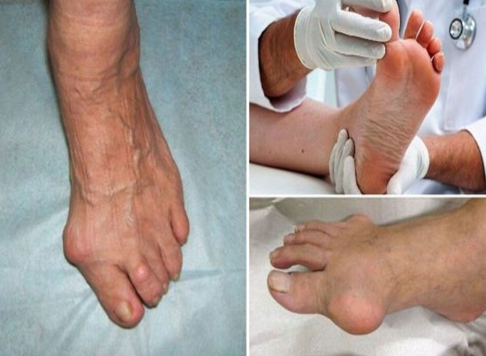

무지외반증 원인

1. 유전적 요인:

일부 사람들은 무지외반증을 유전적으로 가질 수 있습니다. 만일 가족의 어느 누구가 무지외반증을 가지고 있다면, 이를 상속할 가능성이 높아집니다.

2. 부적절한 신발:

협소하거나 높은 힐을 가진 신발을 자주 신으면 발가락이 압력을 받고 무지외반증이 발생할 가능성이 높아집니다. 신발이 발에 맞지 않는 경우 발가락이 압력을 받고 비뚤어질 수 있습니다.

3. 연령:

나이가 들면서 발의 조직은 약해지고 무지외반증이 발생할 가능성이 높아집니다. 특히 골절한 경우 연령이 증가하면 더 큰 위험을 가집니다.

4. 무릎 관절 연골 문제:

무릎의 연골 문제로 인해 보행 패턴이 변하면 발가락에 압력이 가해져 무지외반증이 발생할 수 있습니다.